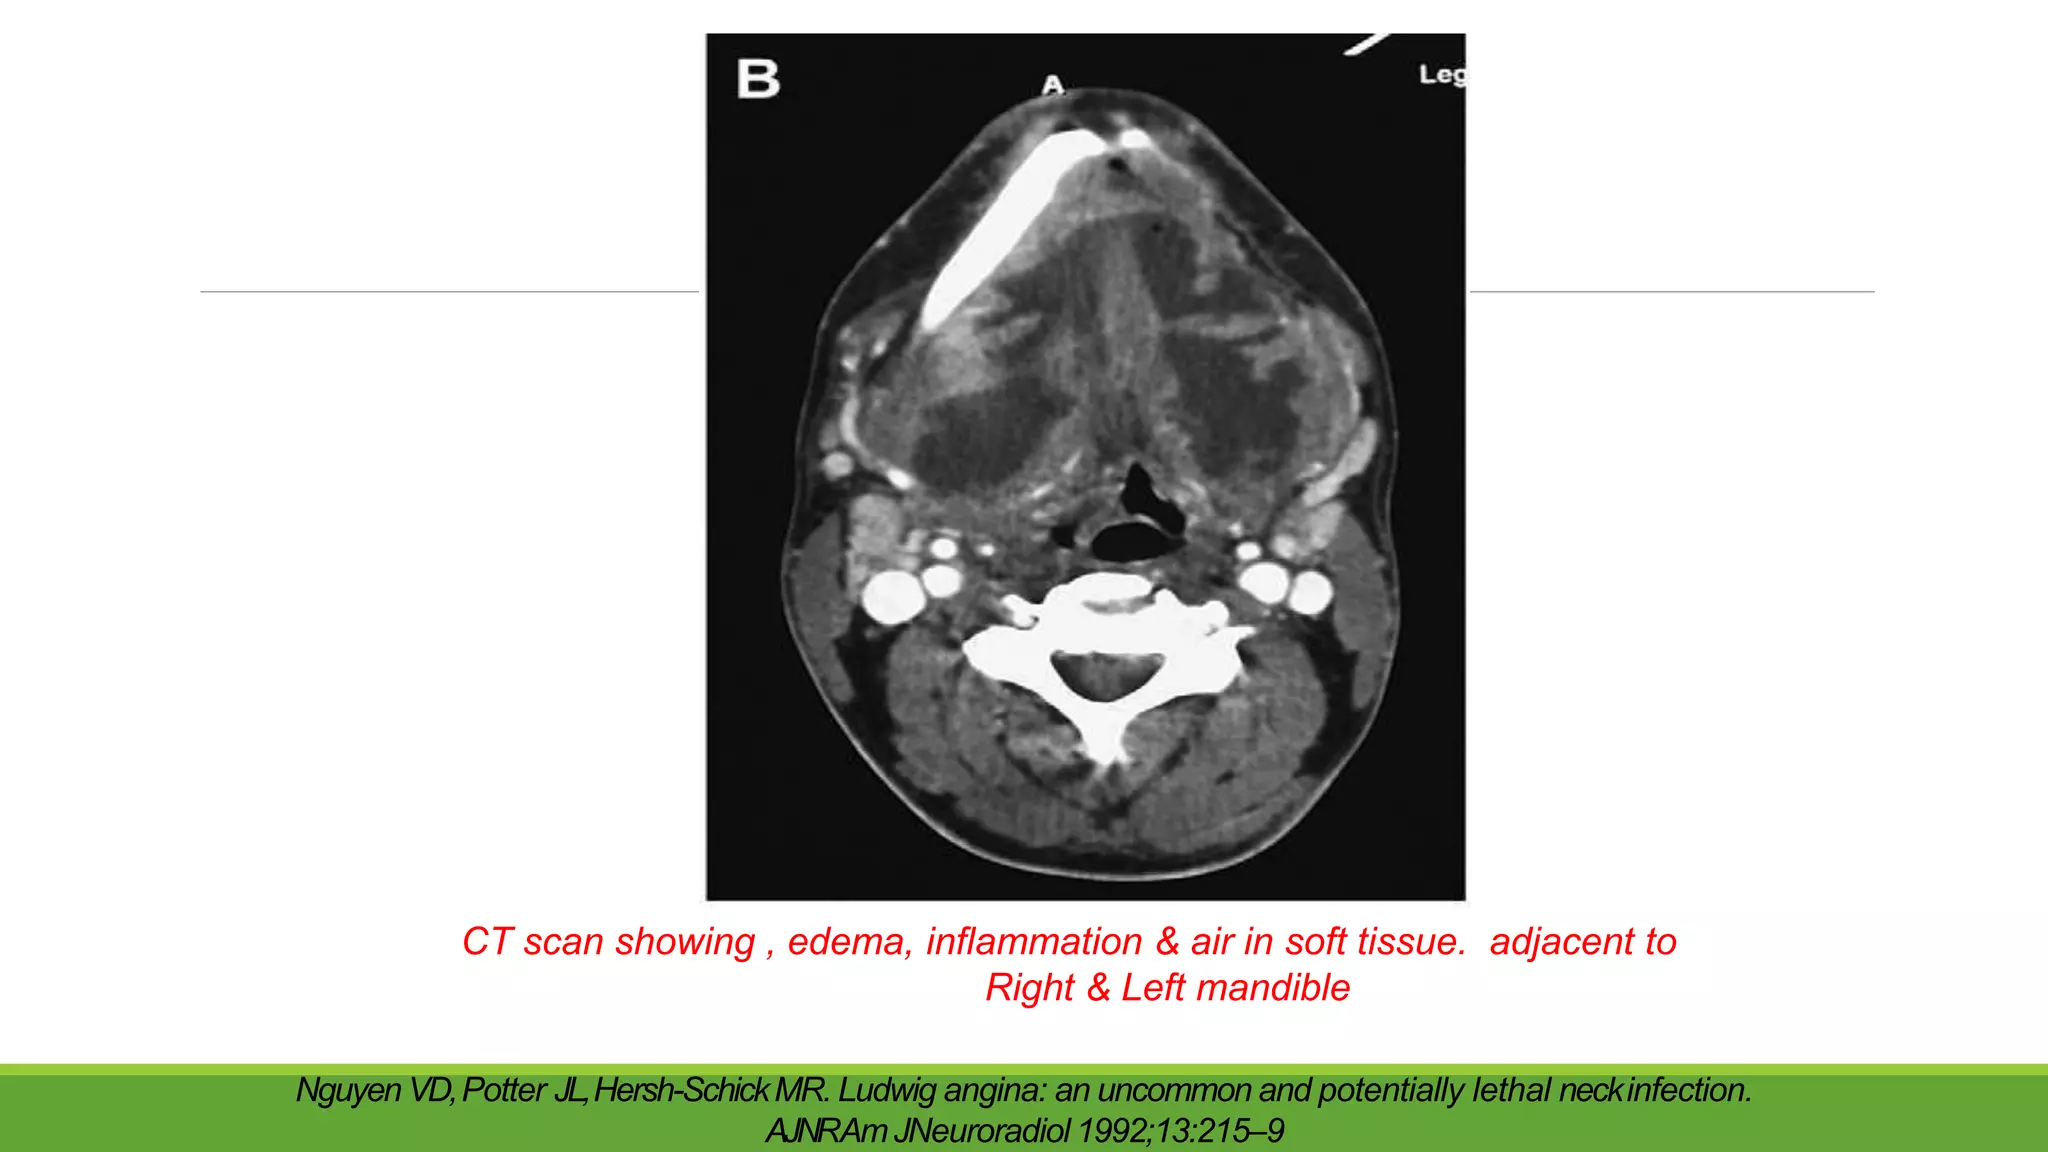

CT scan showing , edema, inflammation & air in soft tissue. adjacent to

Right & Left mandible

Nguyen VD,Potter JL,Hersh-SchickMR. Ludwig angina: an uncommon and potentially lethal neckinfection.

AJNRAmJNeuroradiol 1992;13:215–9